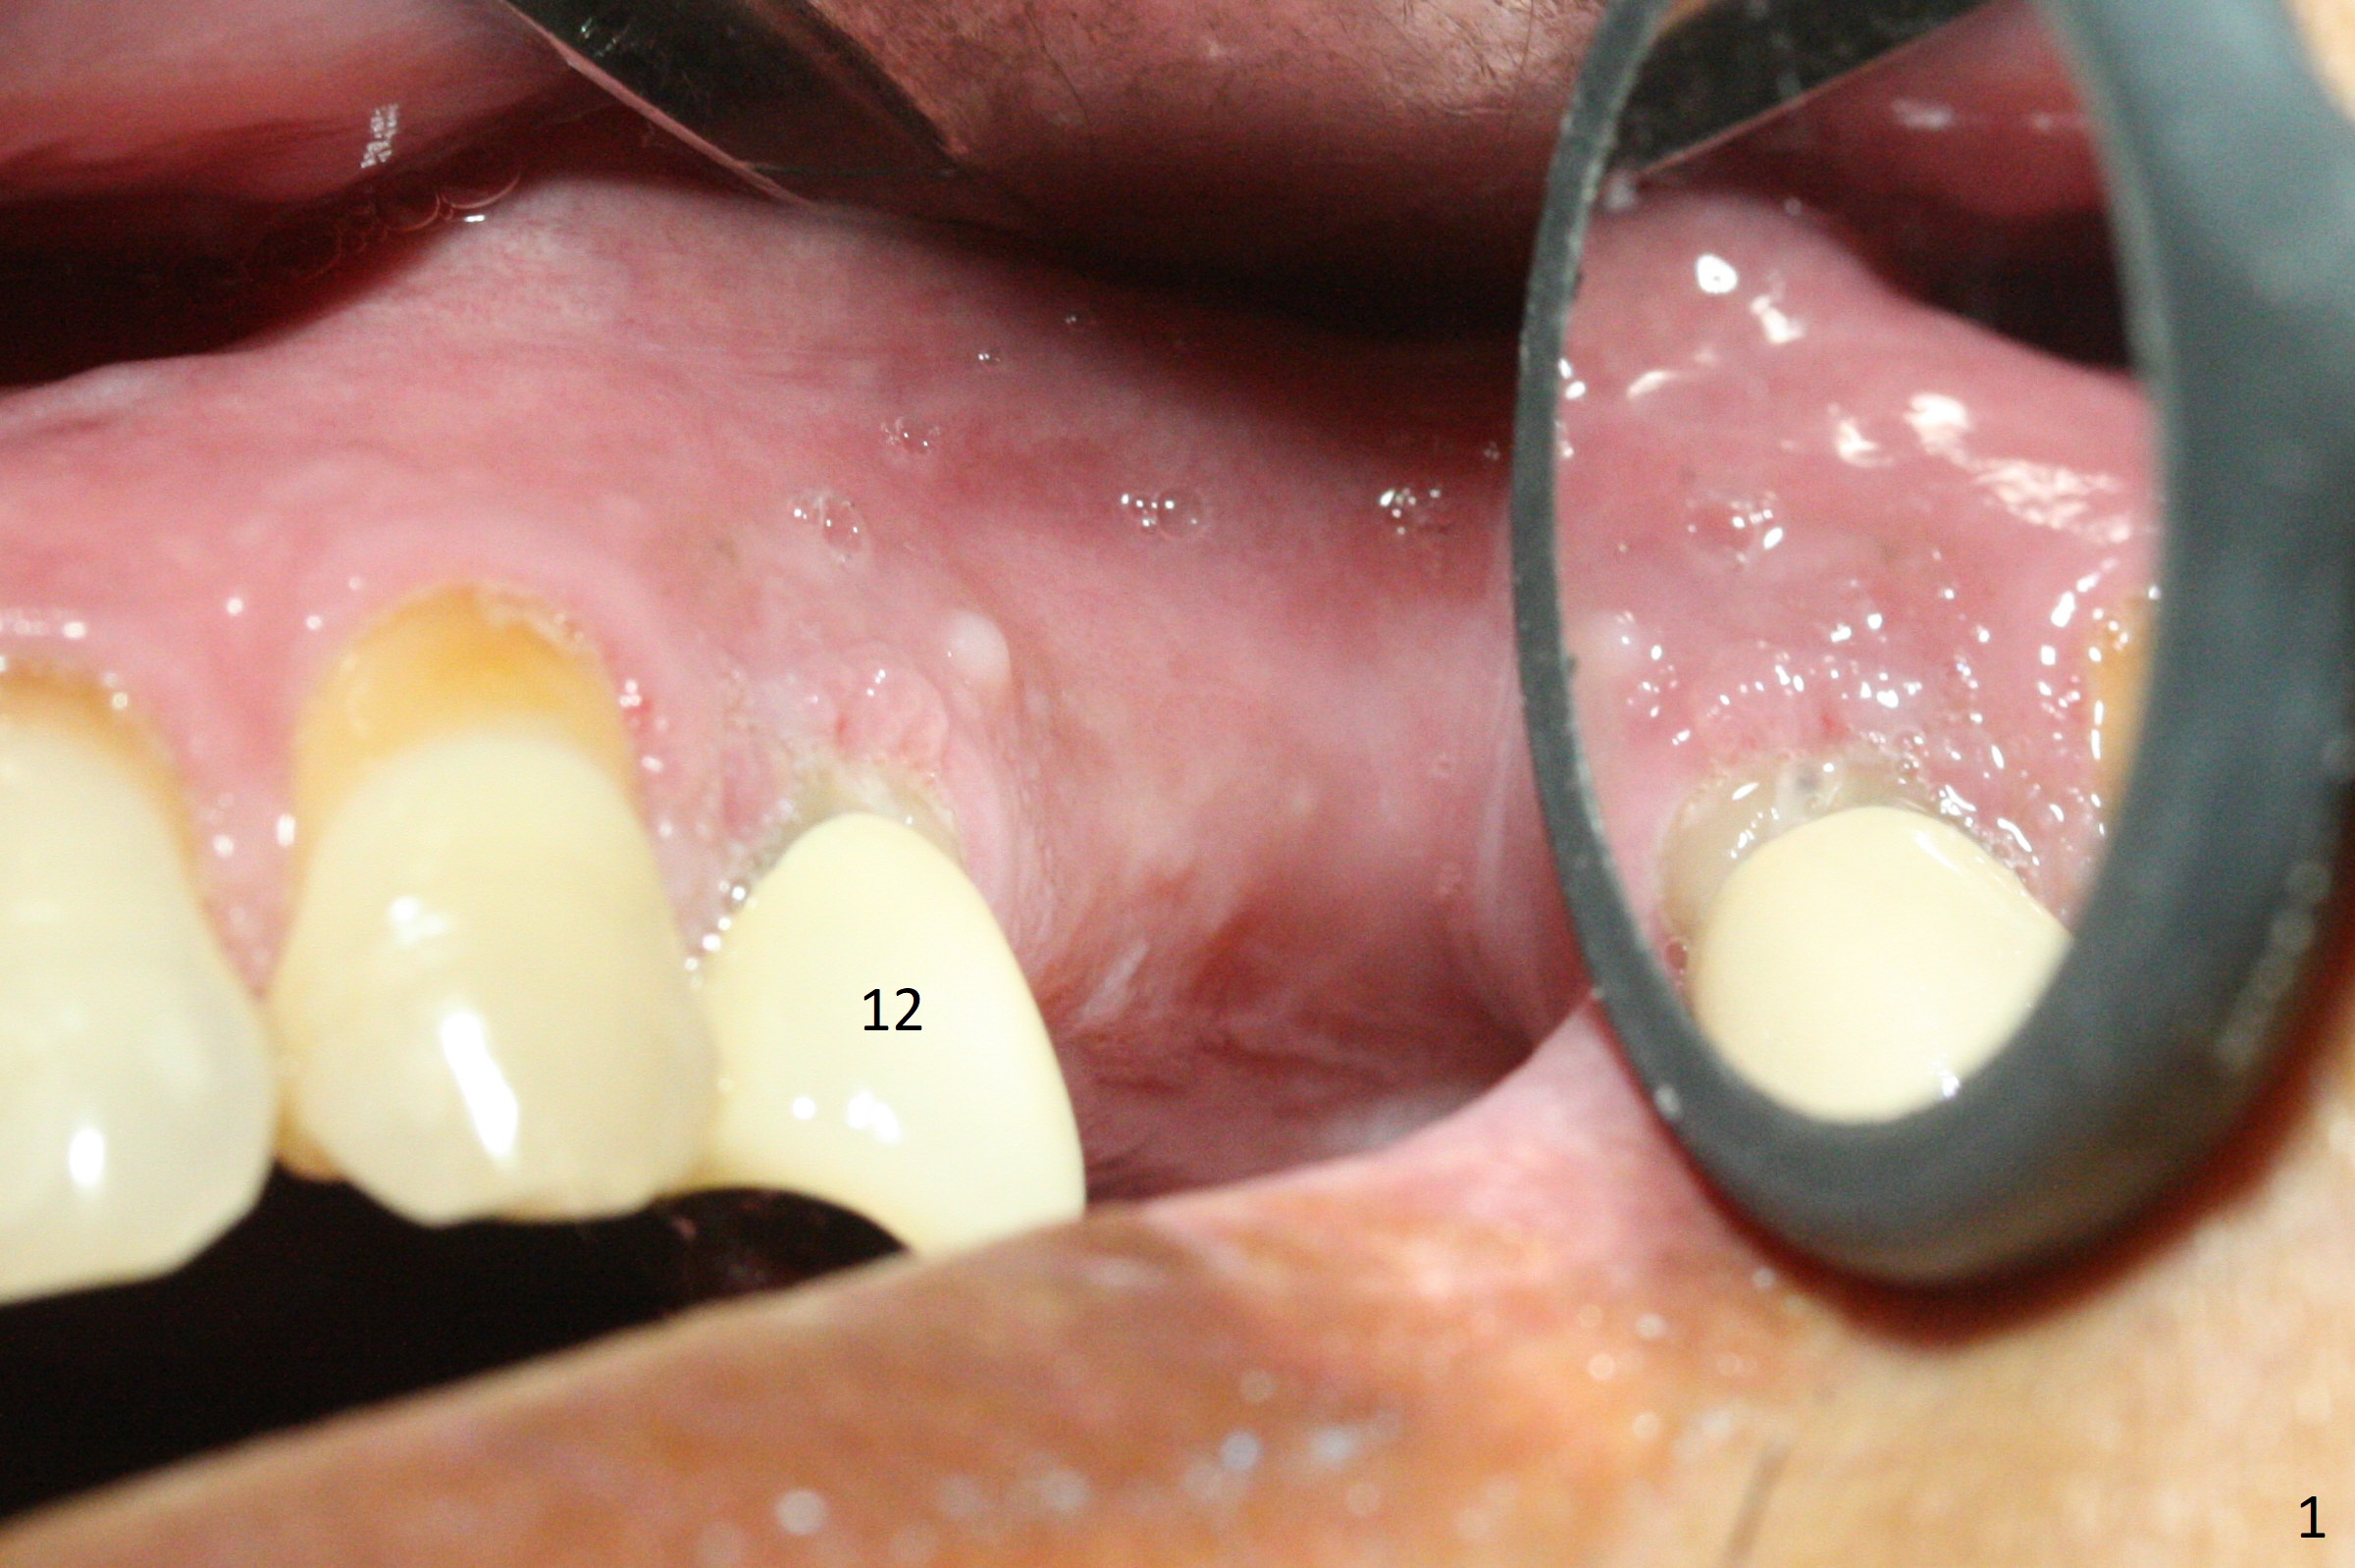

The buccal gingiva at #12 with vertical root fracture looks unhealthy (Fig.1). Osteotomy at #13 is initiated prior to #12 extraction. In fact the osteotomy happens in the extensive defect associated with #12 (Fig.2 red dashed line). To obtain primary stability, the osteotomy at #12 needs to be long, while that at #13 needs two-pointed fixation (Fig.3 *). After adjustment of trajectory at #12 and increase in diameter of the osteotomy at #13 (Fig.4), a 3.8x15 and 3.8x10 mm implants are placed (Fig.5). Following adjustment of implant depth (Fig.6), the implant at #12 becomes loose, while that at #13 tightens. With placement of abutments, an immediate splinted provisional is locked in place to stabilize the loose implant at #12 (Fig.7). The patient complains of cold sensitivity in the upper left quadrant, possibly related to the fact that the implant at #12 is close to the apex of the tooth #11. The position and trajectory of the initial osteotomies should be changed as shown in Fig.8 (white lines, as compared to Fig.2). There is no sensitivity 1 month postop. Impression is taken 4 months postop (Fig.9) after #13 mesiobuccal margin prep. The implants were placed too close to each other. The abutment screw at #13 is retightened 8 months post cementation. There appears no bone loss 9 months post cementation (Fig.10), while the tooth #11 has periapical infection with DL caries 1 year 7 months post cementation (Fig.11).